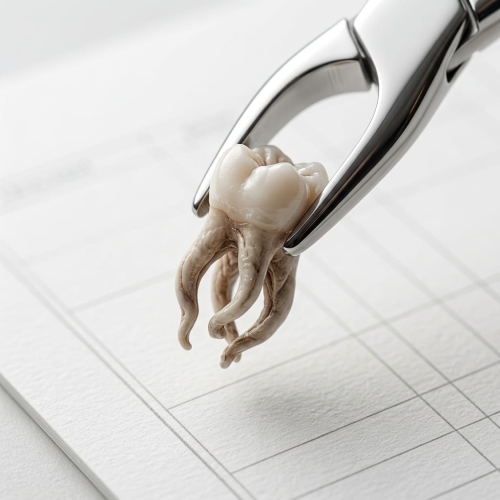

«Неужели снова лечить, если казалось, что всё уже сделано?» – такая мысль приходит многим, кто столкнулся с проблемой некачественного лечения корневых каналов. Сложные каналы, трещины и скрытые устья часто становятся подспорьем для бактерий, и тогда спасение зуба зависит от микроскопа и тонкой работы врача.